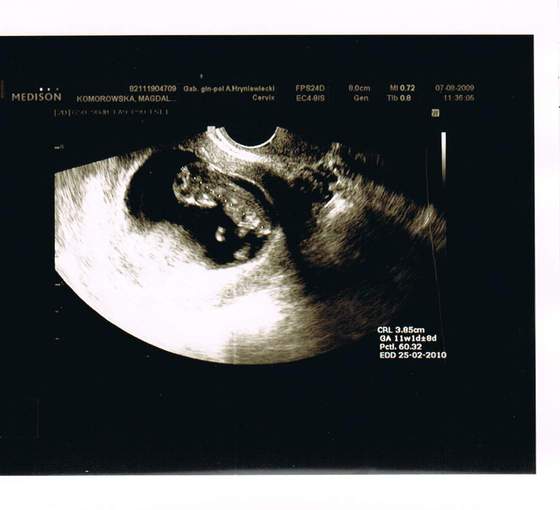

To i ja wrzucam mojego Dzidziola. Jeśli najpierw rozgryzę jak się to robi

Tyle, że mój już nie taki malutki, bo w piątek miał już prawie całe 4cm

Zobacz załącznik 155515

Zdjęcie wkleję później jak M mi zeskanuje